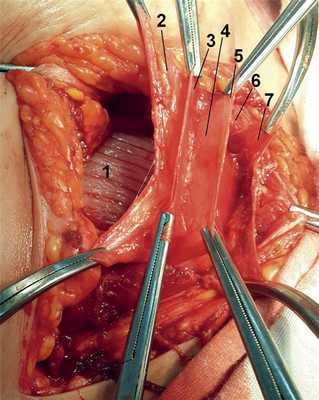

При осуществлении экстраперитонеального оперативного доступа к нижнему сегменту матки после рассечения кожи, подкожной жировой клетчатки и апоневроза широких мышц живота и разведения прямых мышц живота тупым путем обнажается поперечная фасция (рис. 1). Рис. 1. Поперечный надлобковый разрез по Пфанненштилю.

При вскрытии поперечной фасции визуализируется еще 2 тонких пласта ткани, покрывающих спереди и сзади мочевой пузырь (рис. 2). Рис. 2. Интраперитонеальный оперативный доступ. Полость брюшины вскрыта. Кзади от последнего располагается брюшина.

При выполнении диссекции на трупном материале выявлено, что листки пред- и позадипузырной фасций, охватывая мочевой пузырь спереди и сзади, по бокам и выше пупка сливаются в общий листок с поперечной фасцией. От верхушки мочевого пузыря к пупку между предпузырной и позадипузырной фасциями следует урахус (рис. 4). Рис. 4. Поперечный надлобковый разрез по Пфанненштилю. Поперечная фасция (1) вскрыта.

Посредством фасций малый таз разделен на фасциальные клетчаточные пространства. Непосредственно за поперечной фасцией расположено собственно предпузырное клетчаточное пространство. Между листками пред- и позадипузырной фасций и стенкой мочевого пузыря расположено околопузырное пространство. Между брюшиной и позадипузырной фасцией располагается позадипузырное клетчаточное пространство. При наличии в нем хорошо выраженной жировой клетчатки брюшина довольно легко отслаивается от задней стенки мочевого пузыря, что позволяет создать суправезикальный экстраперитонеальный доступ к нижнему сегменту матки. Однако в большинстве случаев это весьма затруднительно, и попытка разделения может осложниться травмой мочевого пузыря. Отпрепаровка брюшины значительно облегчается, если предварительно ножницами рассечь позадипузырную фасцию в поперечном направлении над мочевым пузырем, которая достаточно прочно фиксирует к нему брюшину.